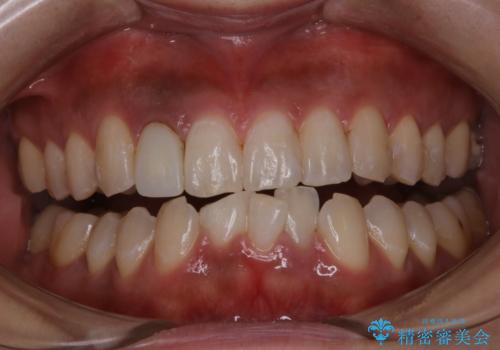

前歯のセラミック作成前にオフィスホワイトニング

- 前歯のセラミックを作る前に、ホワイトニングで全体を白くしたいとのことでした。

効果をより高めるために処置前クリーニング(¥3300)を行ってから、オフィスホワイトニングのエクセレントコース(¥29700)を行いました。

- ¥33000費用は治療当時の料金となります